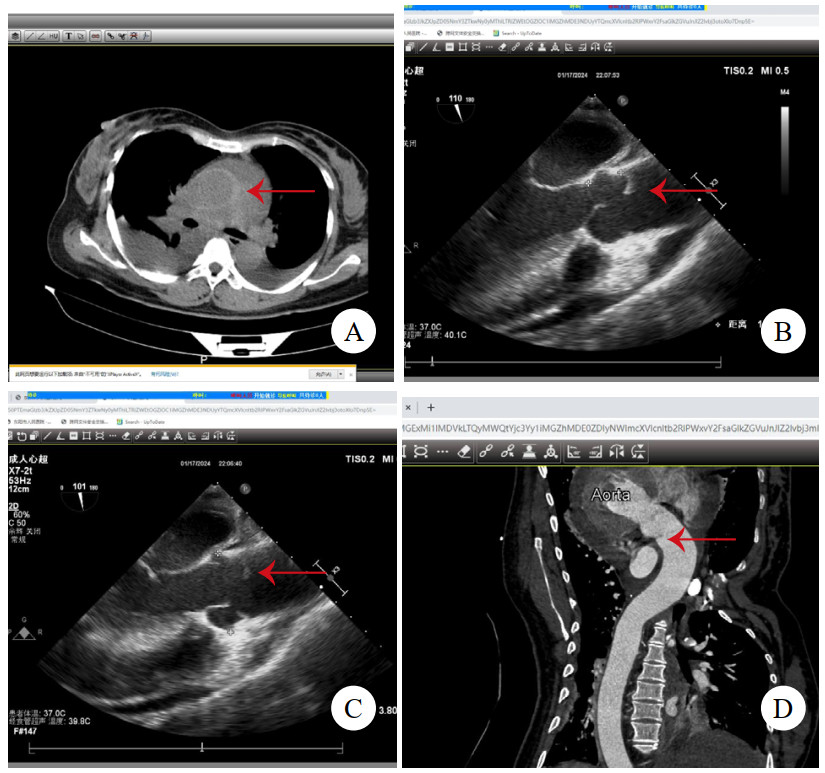

病例3,男,60岁,因“半小时前晕厥1次”就诊。送入抢救室时见患者大汗淋漓,显著呼吸困难,查体:心率97次/min,血压76/52 mmHg(1 mmHg=0.133 kPa),精神极软,颈静脉怒张,心音低钝,未及心脏杂音。立即查床边TTE,见大量心包积液(图 3A)。符合心包填塞,予心包穿刺,见血性液体流出约100 mL后,患者胸闷缓解,心率下降,血压138/88 mmHg。查主动脉CTA,见升弓交界靠上腔静脉侧LIT(图 3B,C,D),该处主动脉直径为31 mm,局部外膜薄层血肿形成。建议手术,患方拒绝,在抢救室留置6 h后生命体征突然消失,后宣布临床死亡。

| 注:A为TTE,箭头示大量心包积液伴血块;B为CTA横断面,箭头示内膜片;C为CTA冠状面,箭头示内膜片;D为CTA多平面重建,箭头示内膜片 图 3 例3患者TTE及CT影像 |